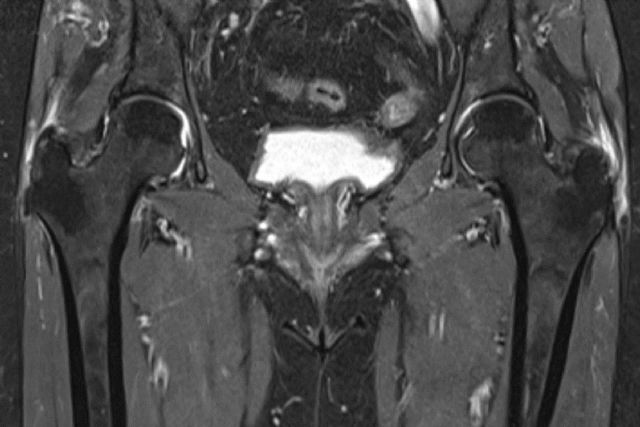

La trocanteritis, también conocida como bursitis trocantérea, es una inflamación de las bursas —pequeñas bolsas llenas de líquido— que se encuentran alrededor del trocánter mayor del fémur. Aunque puede afectar a cualquier persona, es especialmente común en mujeres a partir de los 40 años, corredores y personas que pasan muchas horas de pie o con sobrepeso.

Como explica el Dr. Valero, “cuando la inflamación de la bursa se vuelve crónica o se asocia a lesiones tendinosas, es fundamental realizar un diagnóstico preciso con pruebas de imagen avanzadas y considerar opciones quirúrgicas mínimamente invasivas”.

La artroscopia de cadera permite tratar directamente la causa del dolor —ya sean bursas inflamadas, calcificaciones o fricciones con tendones glúteos— con incisiones mínimas y una recuperación rápida.